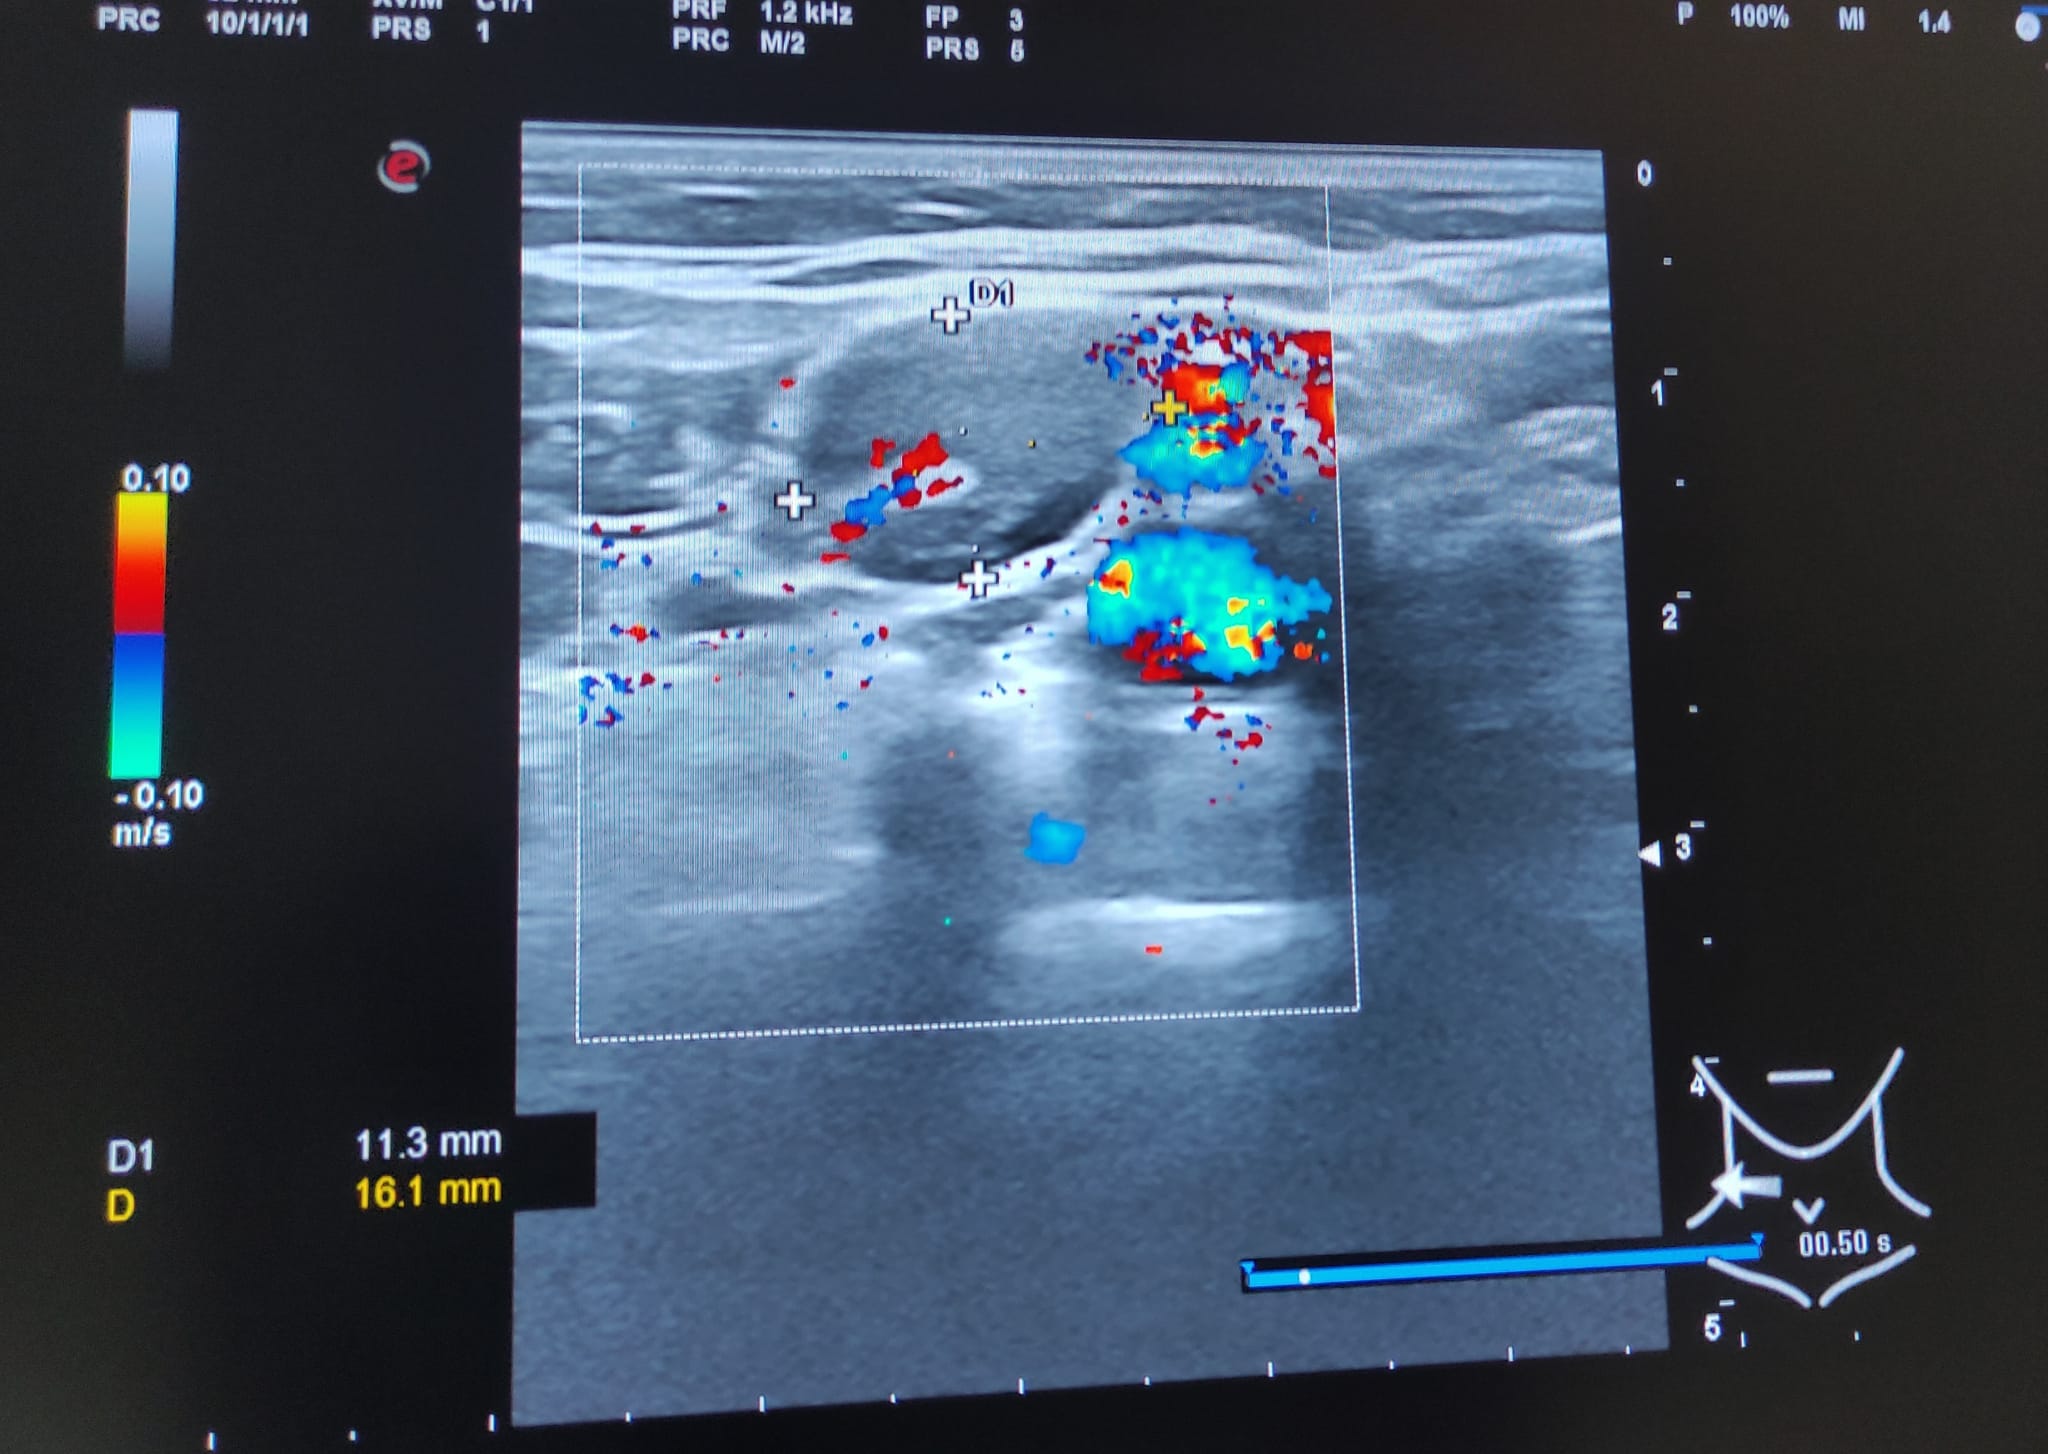

Múltiples adenopatías (más de 12) de varios tamaños siendo la mayor de 2 cm y de morfología redondeada, alguna sin hilio ni centro graso.

A los 3 meses se realiza nueva ecografía sin observar cambios significativos en las adenopatías ya visualizadas. Paciente permanece asintomática.